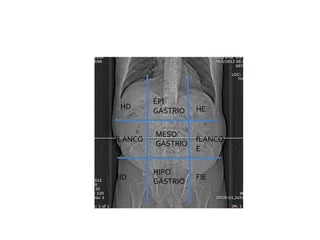

QUADRANTES ABDOMINAIS

HD HE

EPI

GÁSTRIO

fLANCO

D

E

FID FIE

MESO

HIPO